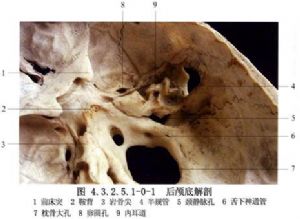

小腦橋腦角前界是顳骨巖部、巖上竇、三叉神經;外側面是巖骨錐體背面、內耳孔和乙狀竇;上方是小腦幕及小腦幕裂孔,中部有面神經與聽神經斜行通過。面神經長約2cm,聽神經瘤時,將面神經向前下擠壓,可拉長達4~5cm;前內側面爲橋腦與延髓,內後面爲小腦半球的側面,下面是舌咽、迷走、副神經,並有小腦下後動脈發出的小動脈支伴行(圖4.3.2.5.1-0-1)。